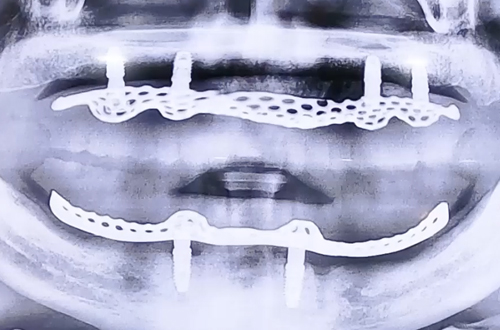

AFTER

전체 임플란트로 치아를 회복시켜줄 때에는 여러 임플란트를 심고 치아 모양의 보철을 따로따로 식립해 주는 방법과, 최소한의 임플란트를 심고 틀니 형태의 보철을 한번에 식립하는 방법이 있는데요.

환자분의 경우 임플란트 틀니를 통한 전체 임플란트를 진행하셨습니다.

임플란트 틀니는 일반 틀니와 달리 임플란트가 틀니를 잡아주기 때문에 고정력이 강하고 모양도 예쁘다는 장점을 가지고 있죠.

이 경우 본래 끼워준 틀니가 양옆과 앞뒤 모든 방향으로 흔들림이 없도록 최소 4개 이상의 임플란트를 식립하는데, 환자분은 아랫니를 발치한지 오래되어 잇몸뼈가 퇴축된 상태로, 임플란트를 심을 공간이 부족해 어쩔 수 없이 2개만으로 진행하기로 결정하고 치료가 시작되었습니다.

임플란트를 심은 후 임플란트 틀니를 제작해 식립하여 드렸으며, 앞으로 6개월마다 한번씩 정기검진을 통해 꾸준히 관리해 드릴 예정입니다. ^^